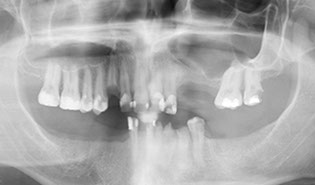

ii) Treatment Planning, including 3d cone beam scans

Your diagnosis includes a thorough radiographic examination. Brener Clinic takes 3D Cone Beam CT Scans as well as digital impressions of your upper and lower jaws to assist with treatment planning. A thorough medical history is also taken so we can communicate with your doctor and specialist medical team if necessary.